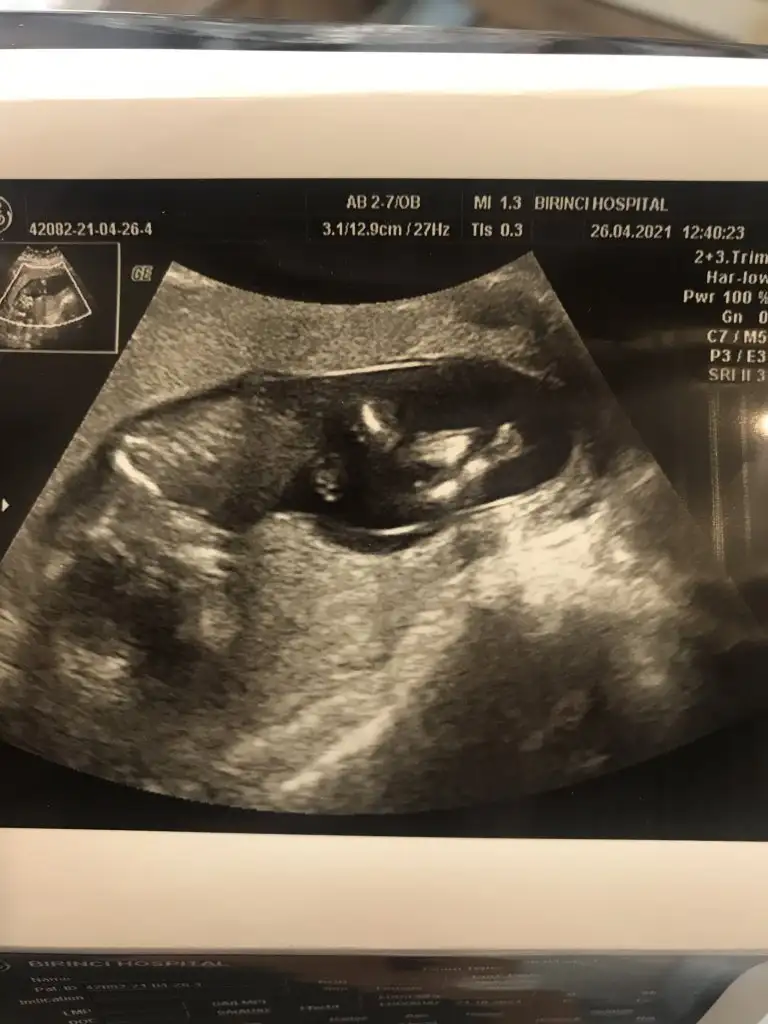

Bana da bakarmisiniz lutfen 🙏🙏

Benim 6+4 de bi sag da bi solda gorundu..

7+6 goruntude ortada gorundu... hepsi de karından 🙏